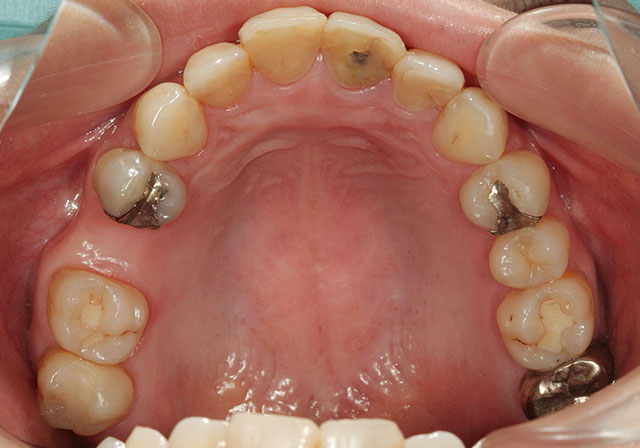

Before